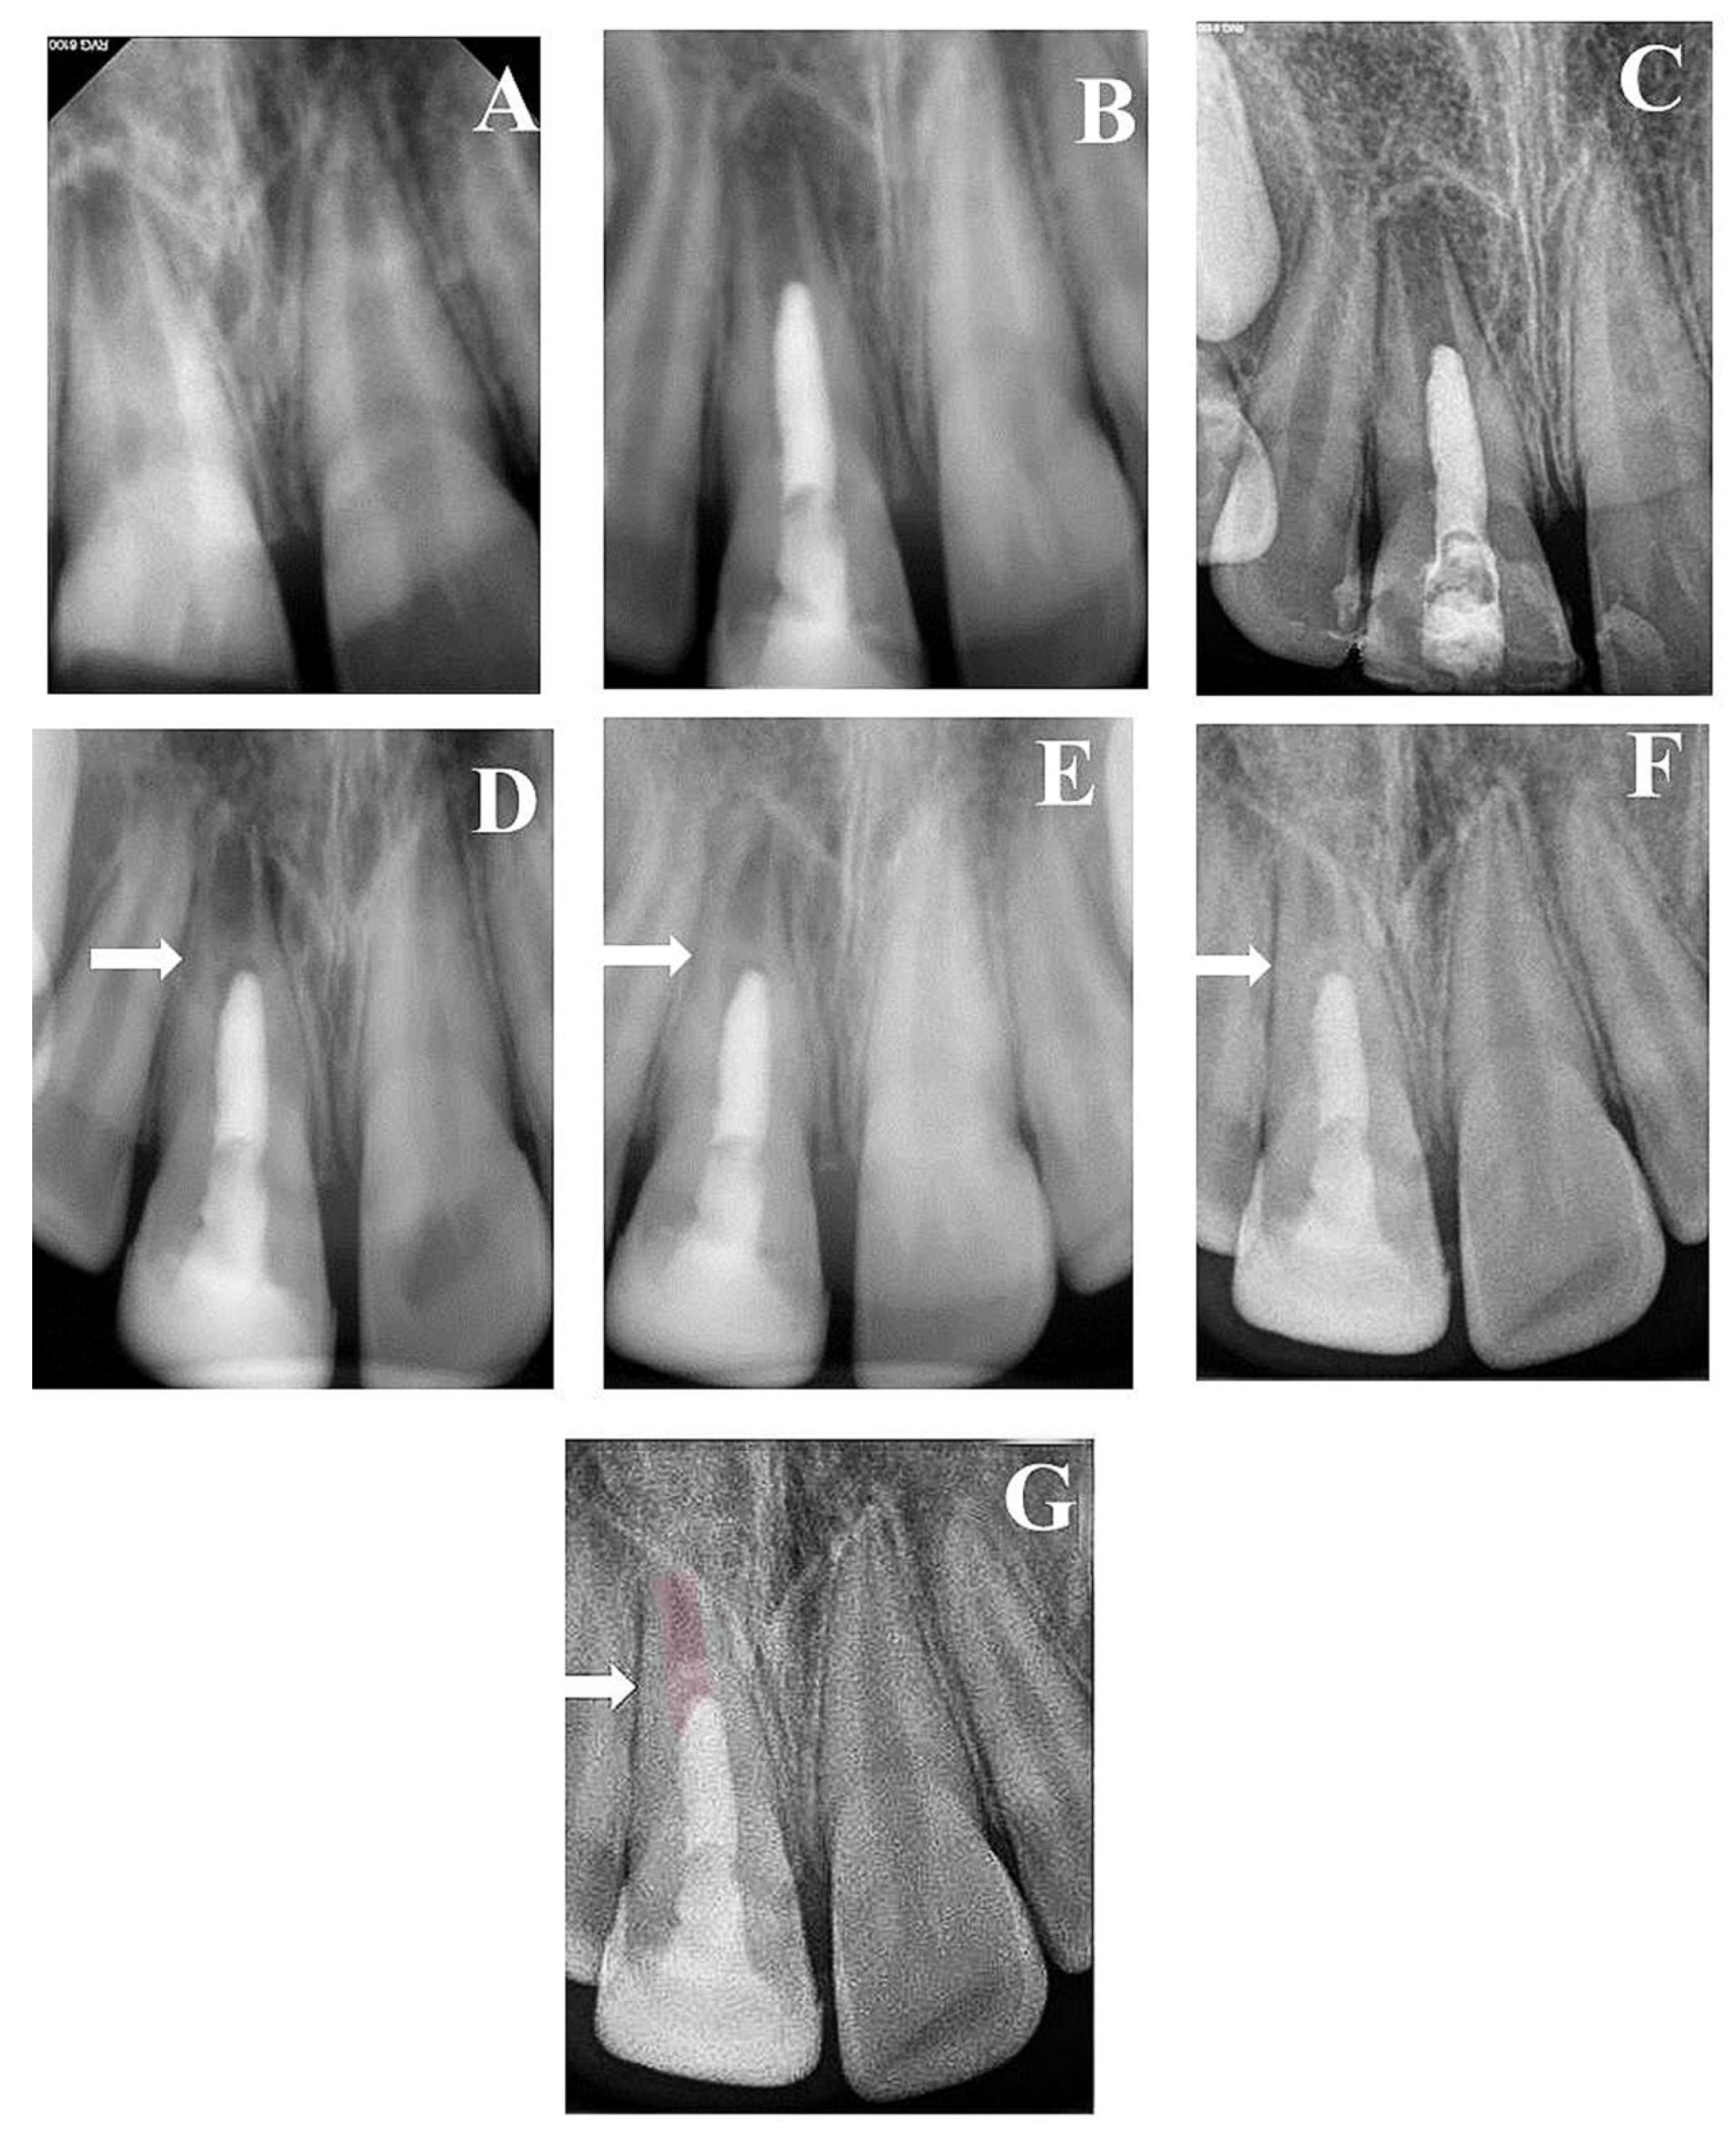

3. Results

3.1. Quantitative Assessment

3.2. Qualitative Assessment